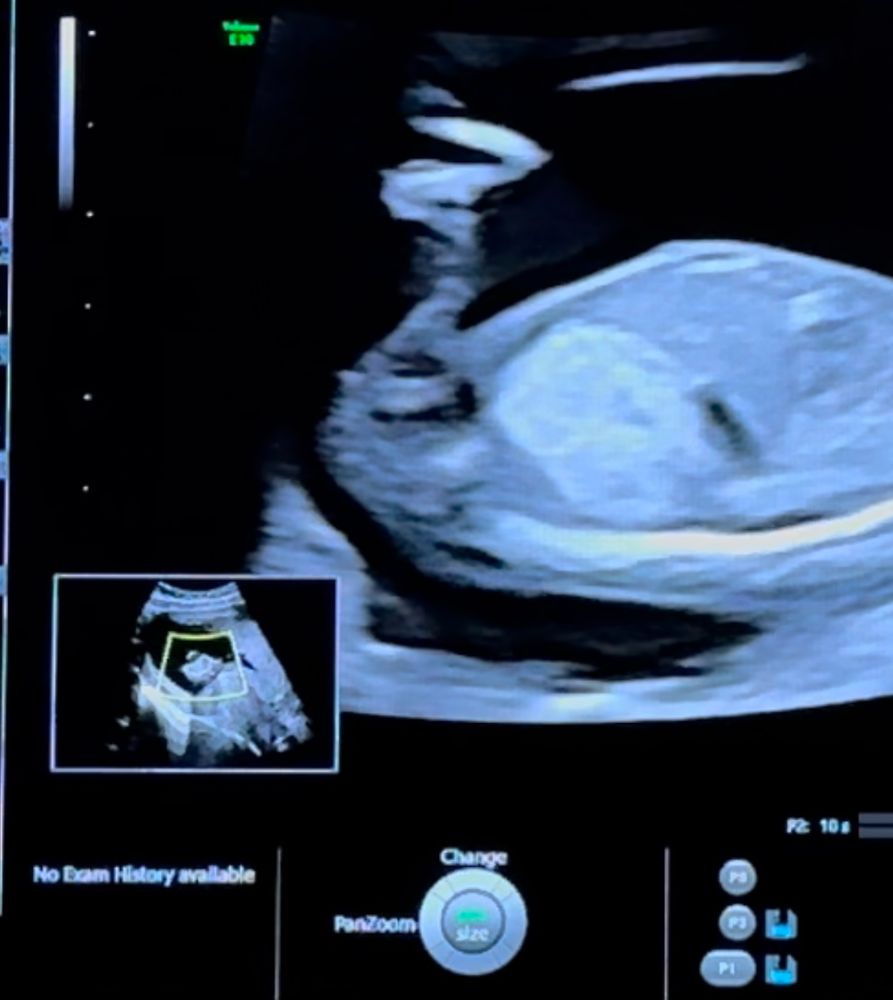

Половой бугорок (пол 12 недель)

это половой бугорок торчит? Кто умеет определять?) девочка или мальчик

Мальчик

У меня с 1 скрининга (11 где-то неделя) очень похожий снимок

У меня сын 👐🏻